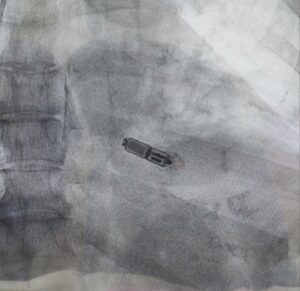

इन सभी जोखिमों को ध्यान में रखते हुए ITSA Hospital की कार्डियोलॉजी टीम ने मेडट्रॉनिक माइक्रा AV2 लीडलेस पेसमेकर का चयन किया। यह तकनीक दुनिया की सबसे उन्नत पेसिंग तकनीकों में से एक है और भारत में अभी भी सीमित केंद्रों पर ही उपलब्ध है।

यह डिवाइस पैर की नस के माध्यम से सीधे हृदय में प्रत्यारोपित की जाती है, जिससे छाती पर किसी भी प्रकार की ओपन सर्जरी की आवश्यकता नहीं पड़ती।

आकार में बेहद छोटा, लगभग एक विटामिन कैप्सूल के बराबर